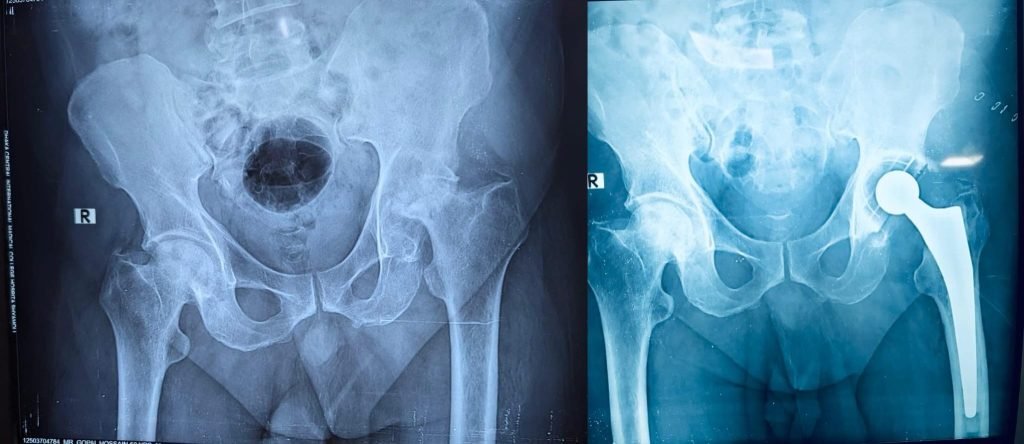

52 years old male having ankylosed right hip with fracture neck of femur. Un cemented total hip replacement done